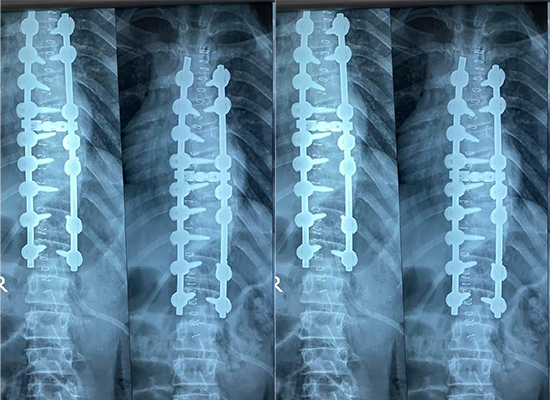

L'imagerie postopératoire a démontré un alignement amélioré de la colonne vertébrale par rapport à l'état préopératoire. La construction de fixation semblait stable, supportant la correction souhaitée. Selon l'équipe chirurgicale, le patient a présenté une récupération postopératoire satisfaisante, sans aucune complication immédiate liée à la fixation.

Ce cas de correction de scoliose de Dhaka, au Bangladesh, démontre l'application clinique d'un système de vis pédiculaires de 6,0 mm dans la chirurgie de la déformation de la colonne vertébrale chez l'adolescent. Le cas met en évidence des éléments clés, notamment la fixation segmentaire, la correction contrôlée des déformations et un alignement postopératoire stable.

L'alignement de la colonne vertébrale a été évalué à l'aide d'études d'imagerie avant la chirurgie et d'évaluations radiographiques postopératoires pour confirmer la stabilité de la correction et de la fixation.

L'imagerie postopératoire a montré une amélioration de l'alignement de la colonne vertébrale et le patient a démontré une récupération satisfaisante avec une fixation interne stable.